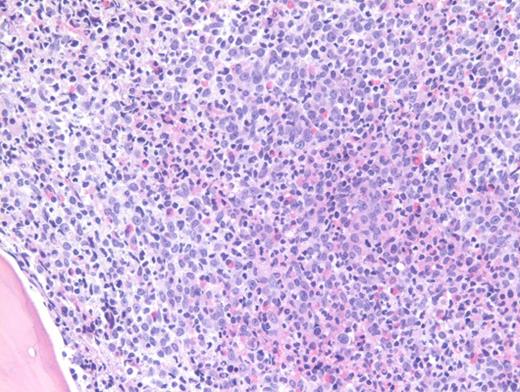

A previously healthy 27-year-old man presented to an outside hospital with bilateral ear aches and prescribed a short course of antibiotics with a working diagnosis of bilateral otitis media. Two weeks later, he presented to an outside hospital emergency department with syncope and was transferred immediately to our hospital for further care. During admission, on physical examination the patient was noted to have palpable splenomegaly. Laboratory tests performed were notable for a white blood cell count of 103.9 × 103/μL, hemoglobin of 8.1 g/dL, and platelets of 99 × 103/μL. Abnormal circulating cells were present in significant numbers (45%, black arrow; 12%, grey arrow). However, reverse transcriptase–polymerase chain reaction for BCR-ABL detected only very low numbers of both p210 and p190 transcripts. The images shown here are of a Giemsa-stained peripheral blood smear (Figure 1 [low power] and Figure 2 [high power]), hematoxylin and eosin stained bone marrow core biopsy (Figure 3), and CD61 immunostain on core biopsy for megakaryocytes (Figure 4).

Chronic myelogenous leukemia (CML) in blast phase is defined by having 20 percent or more blasts in the peripheral blood or bone marrow or the finding of extramedullary blasts. However, this case in particular does not have the characteristic blast count, but rather the combination of findings including anemia, thrombocytopenia, marked basophilia, an additional Ph copy in conjunction with circulating blasts, and large focal clusters of medullary blasts that is consistent with blast phase. It has been suggested that blasts occupying an entire trabecular space or more, as seen in this case, can be considered presumptive evidence of blast phase even if the remaining marrow shows chronic phase.1 The CD61 immunostain highlights dwarf forms of megakaryocytes consistent with the CML diagnosis. Prominent fibrosis in this case resulted in a dry tap precluding an effective blast count, and CD34 immunostain was largely negative indicating a CD34-negative blast transformation. About 5 percent of cases present in accelerated or blast phase without a preceding chronic phase.